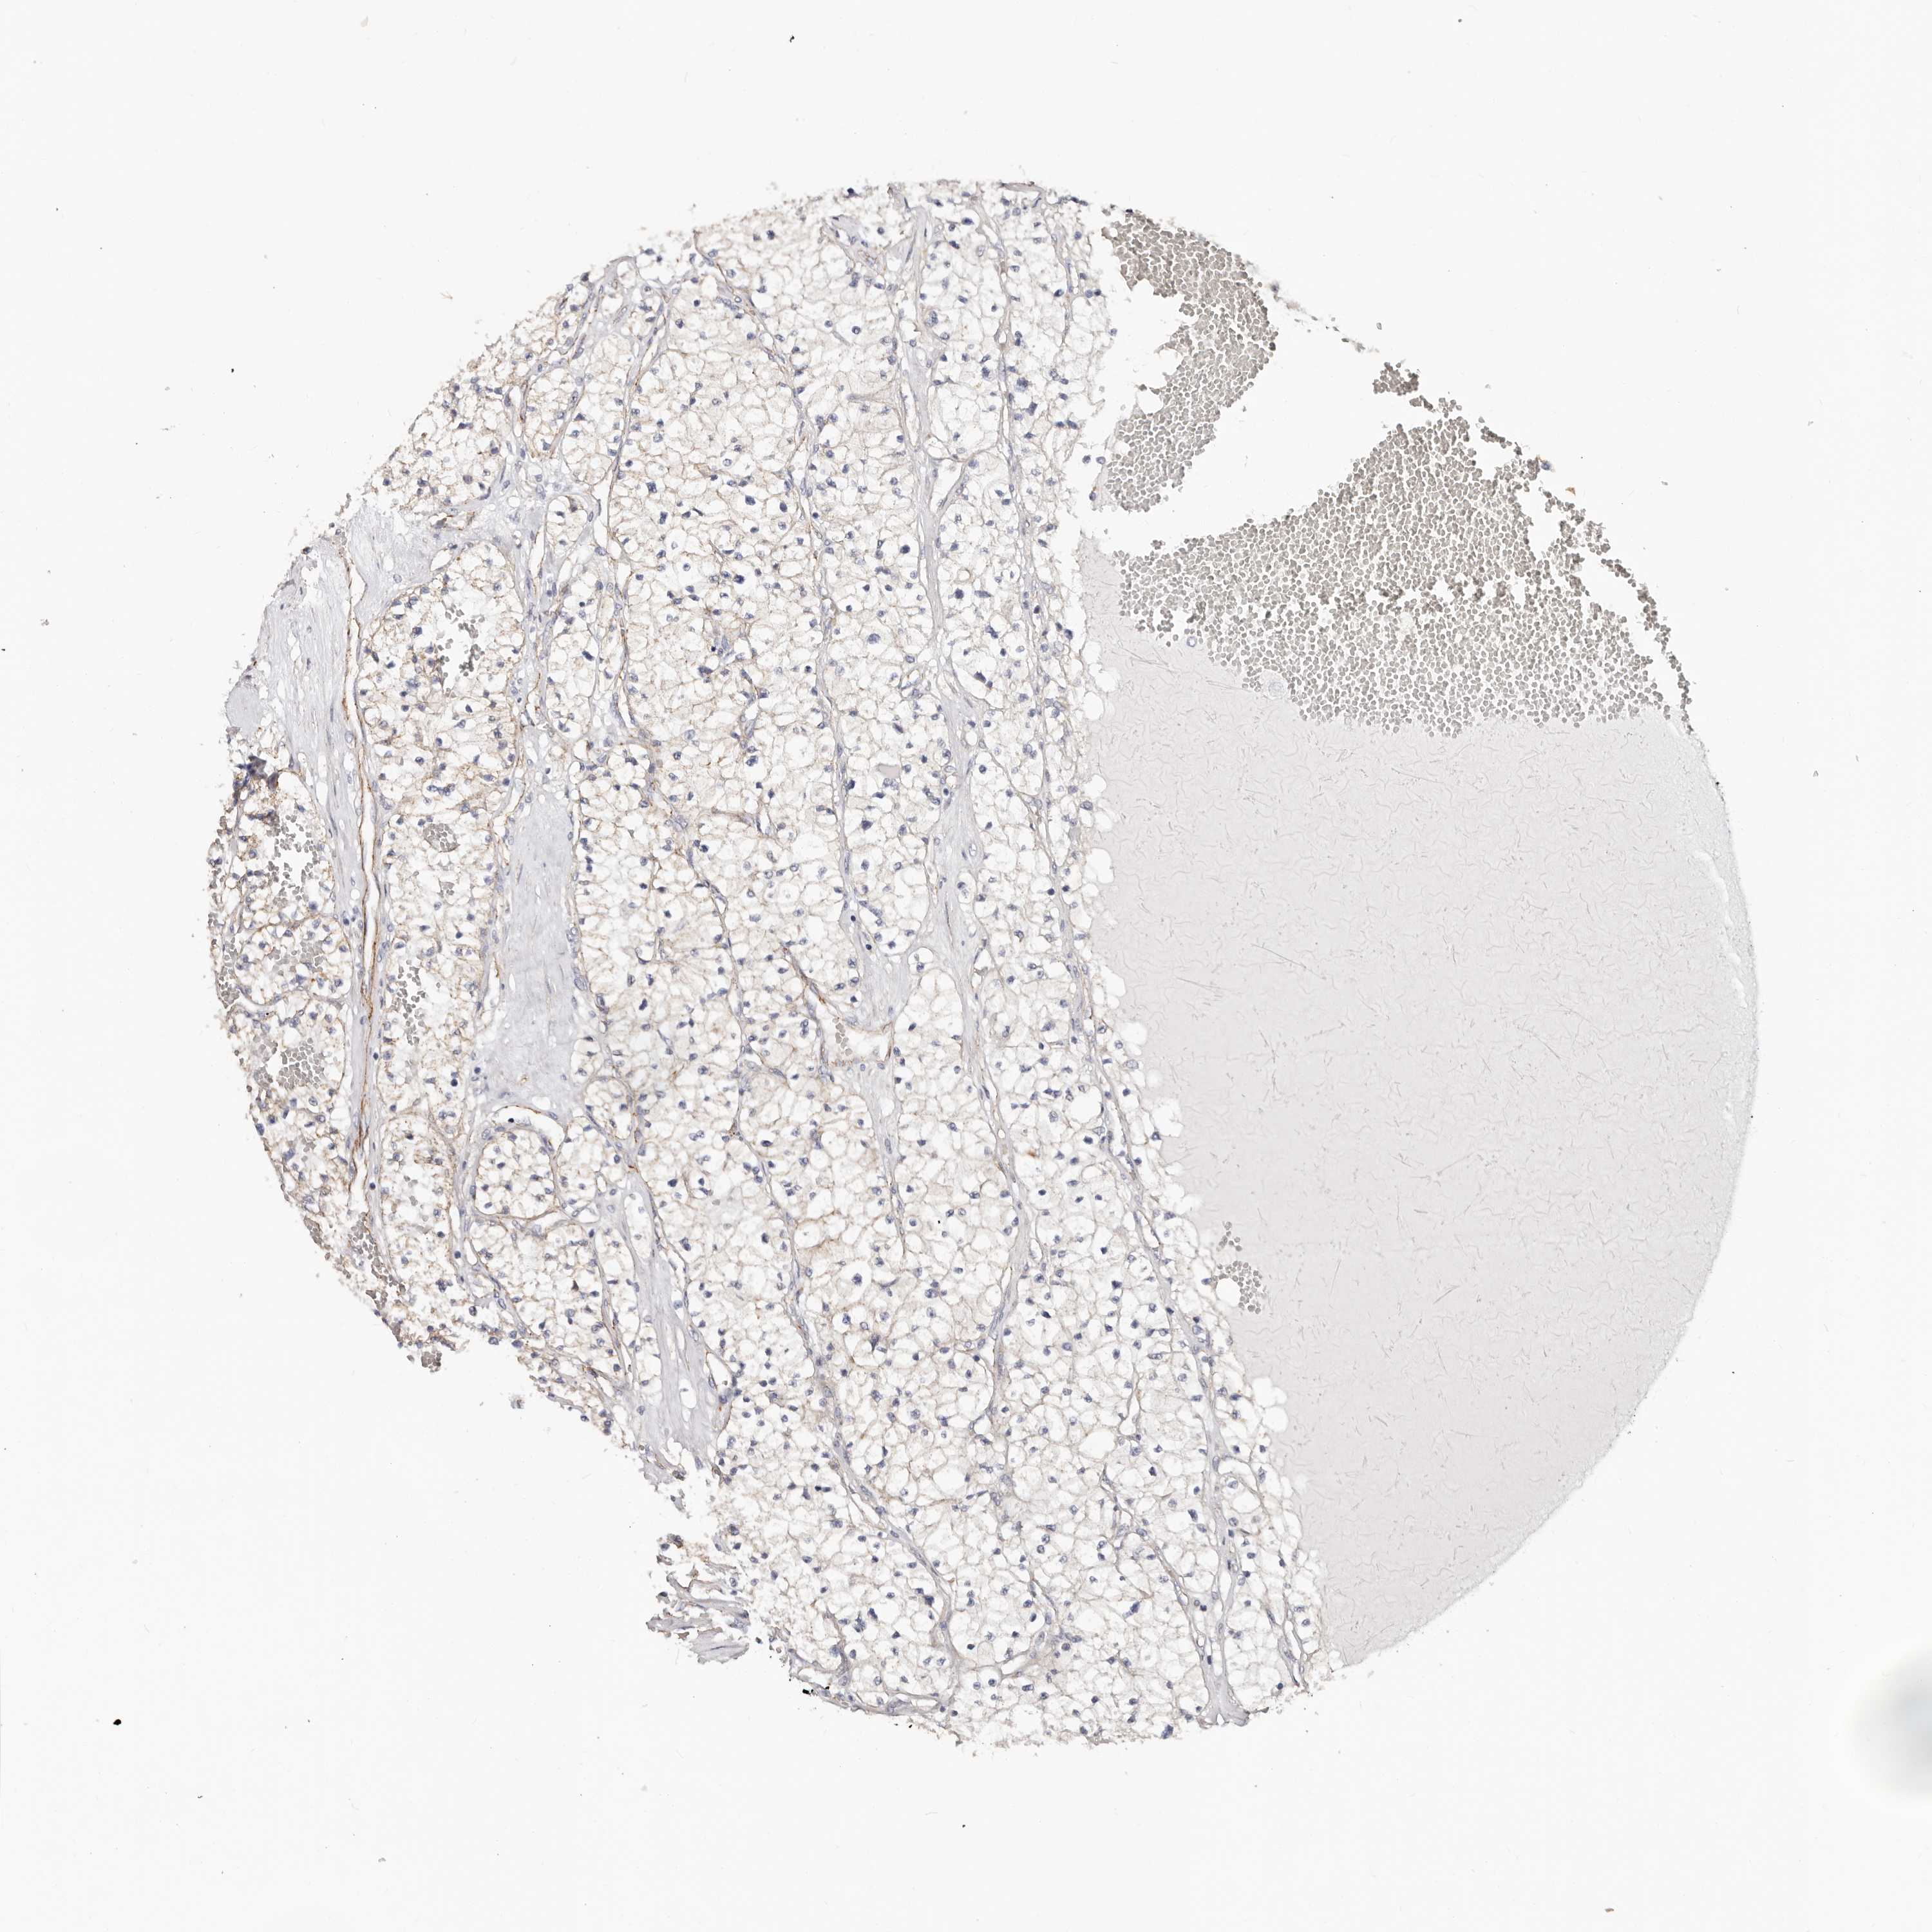

KIDNEY RENAL CLEAR CELL CARCINOMA (VALIDATION) - Interactive survival scatter ploti

The Survival Scatter plot shows the clinical status (i.e. dead or alive) for all individuals in the patient cohort, based on the same data that underlies the corresponding Kaplan-Meier plots. Patients that are alive at last time for follow-up are shown in blue and patients who have died during the study are shown in red.

The x-axis shows the expression levels (FPKM) of the investigated gene in the tumor tissue at the time of diagnosis. The y-axis shows the follow-up time after diagnosis (years). Both axes are complimented with kernel density curves demonstrating the data density over the axes. The top density plot shows the expression levels (FPKM) distribution among dead (red) and alive patients (blue). The right density plot shows the data density of the survived years of dead patients with high and low expression levels respectively, stratified using the cutoff indicated by the vertical dashed line through the Survival Scatter plot. This cutoff is automatically defined based on the FPKM cutoff that minimizes the p-score. The cutoff can be changed by dragging the vertical line or by entering a cutoff value in the square labeled "Current cut-off".

Under the Survival Scatter plot the p-score landscape (black curve; left axis) is shown together with dead median separation (red curve; right axis). Dead median separation is the difference in median mRNA expression between patients who have died with high and low expression, respectively. It is calculated as follows: median FPKM expression of dead patients with high expression - median FPKM expression of dead patients with low expression. This is intended to aid the user in visually exploring custom cutoffs and the associated p-scores and dead median separation.

Individual patient data is displayed and can be filtered by clicking on one or more of the category buttons on the top of the page. Categories describing expression level and patient information include: high, low, alive, dead, female, male and tumor stages. The scale of the x-axis can be toggled between linear and log-scale by clicking on the "x log" button. Mouse-over function shows TCGA ID, patient information and mRNA expression (FPKM) for each patient.

& Survival analysisi

Kaplan-Meier plots summarize results from analysis of correlation between mRNA expression level and patient survival. Patients were divided based on level of expression into one of the two groups "low" (under cut off) or "high" (over cut off). X-axis shows time for survival (years) and y-axis shows the probability of survival, where 1.0 corresponds to 100 percent.

CTNNB1 is validated prognostic, high expression is favorable in Kidney Renal Clear Cell Carcinoma (validation)

Best expression cut offi

Based on the FPKM value of each gene, patients were classified into two groups and association between prognosis (survival) and gene expression (FPKM) was examined. The best expression cut-off refers the FPKM value that yields maximal difference with regard to survival between the two groups at the lowest log-rank P-value. Best expression cut-off was selected based on survival analysis .

When clicking on this number, the vertical dashed line indicating cut-off, the interactive survival plot, and the Kaplan-Meier curve will be adjusted to show results based on the best expression cut-off.

: 154.2

TCGA RNA samplesi

RNA-seq data is reported as average FPKM (number Fragments Per Kilobase of exon per Million reads), generated by the The Cancer Genome Atlas (TCGA) .

Normal distribution across the dataset is visualized with box plots, shown as median and 25th and 75th percentiles. Points are displayed as outliers if they are above or below 1.5 times the interquartile range. FPKM values of the individual samples are presented next to the box plot.

Average pTPM 158.3

Number of samples 100